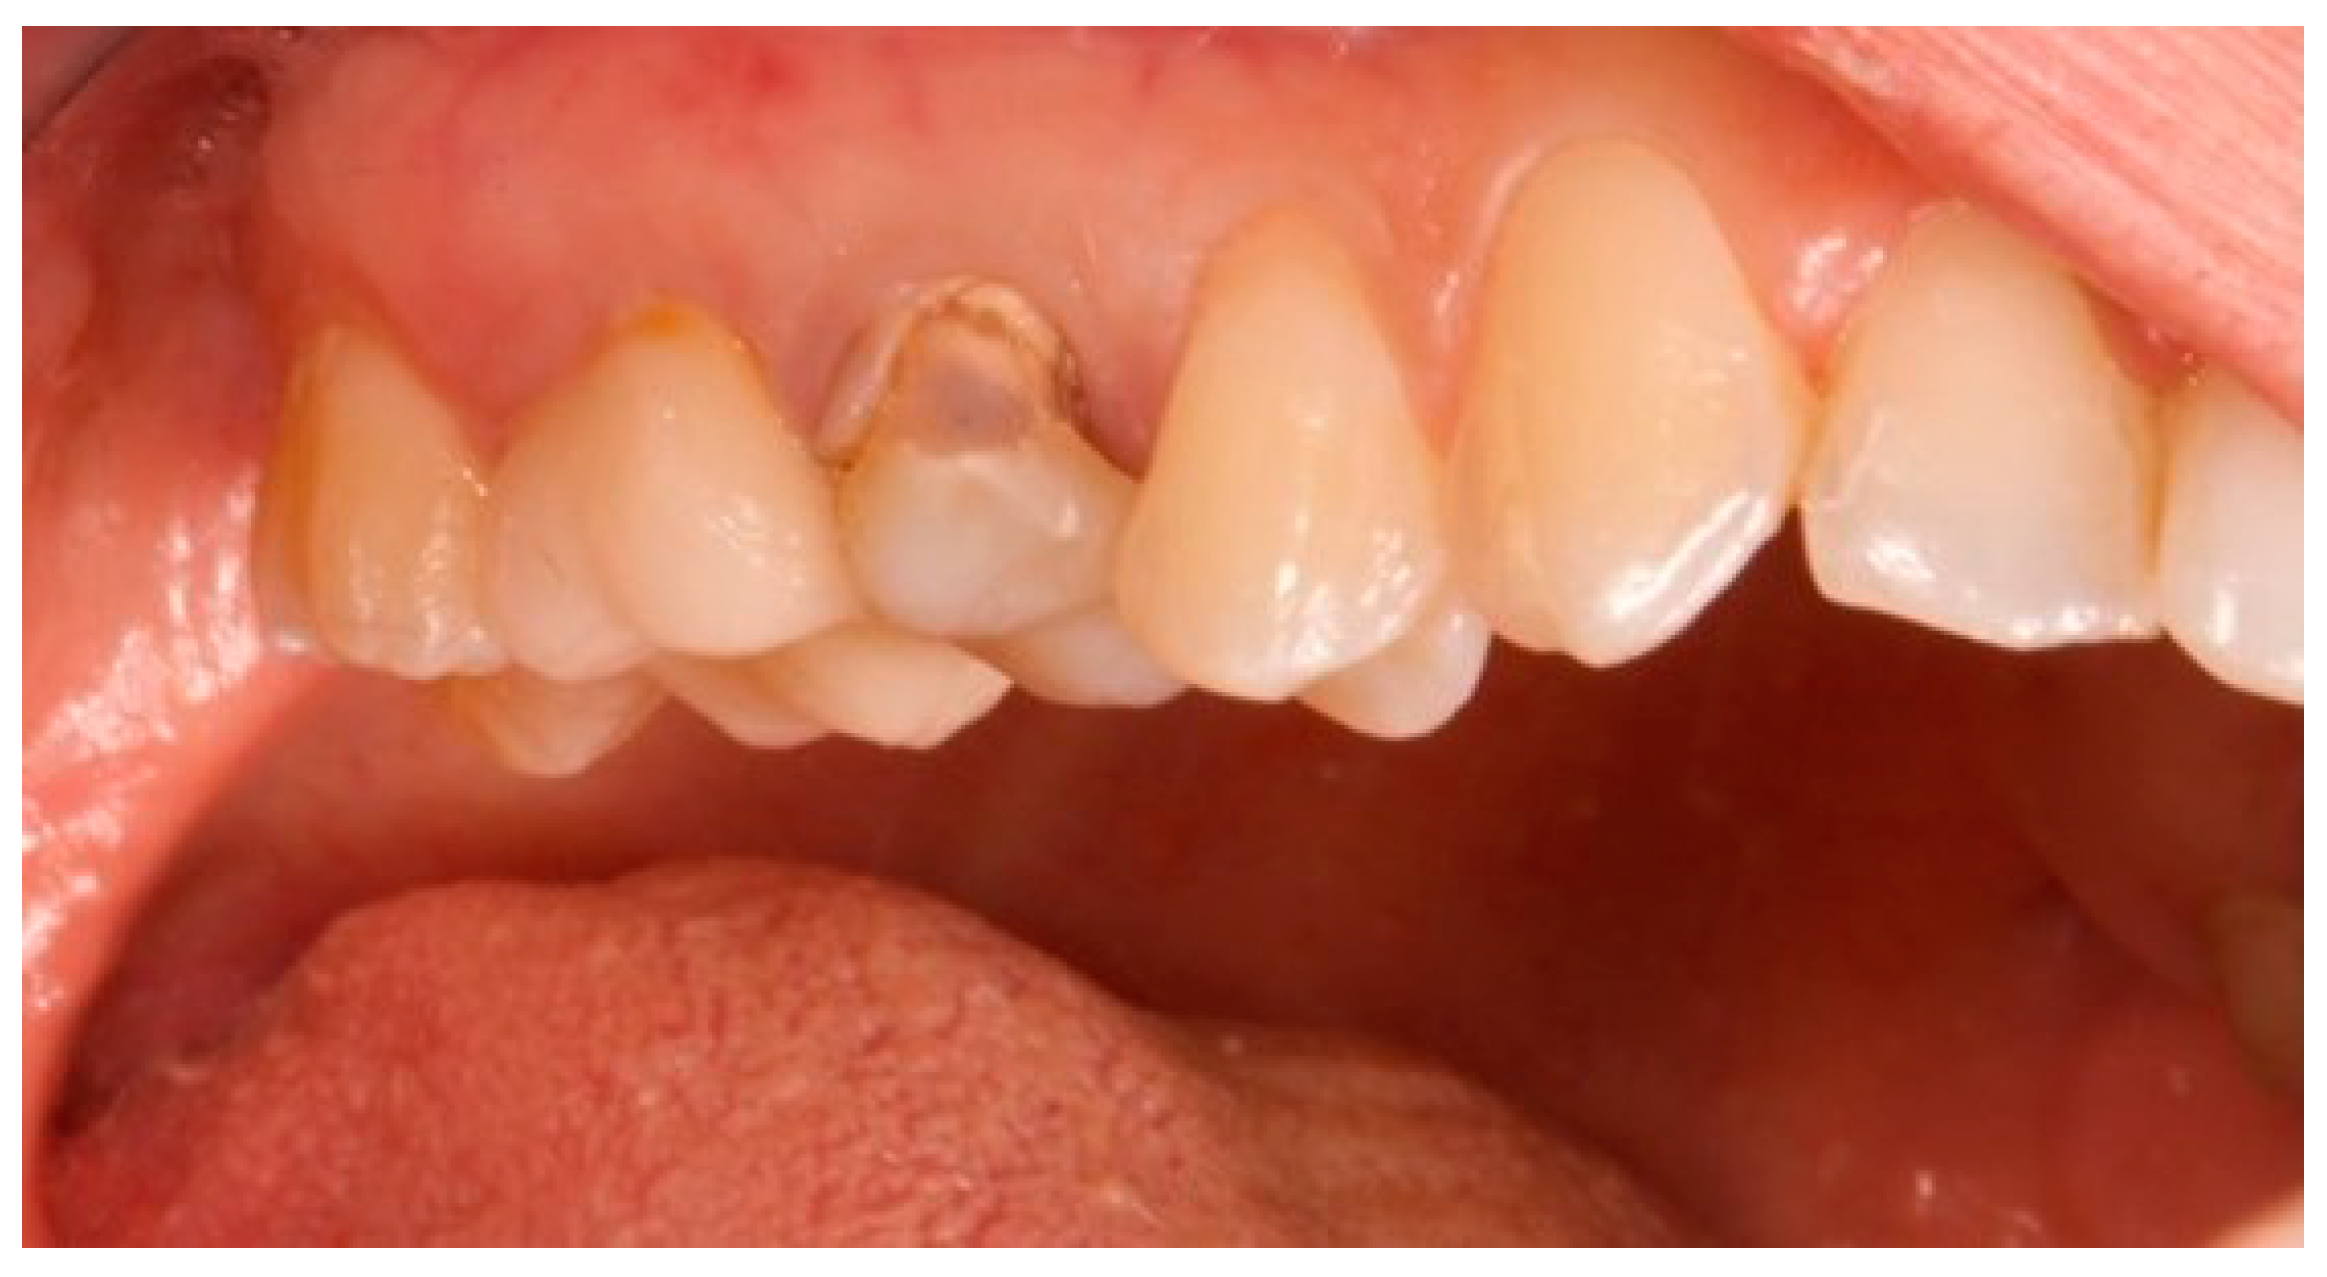

Figure 6.

Healing abutment in situ after implant insertion.

This attention to detail ensured precise fit and optimal soft tissue healing around the abutment.